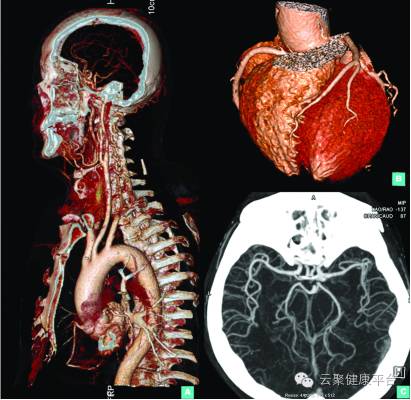

CT之剑中剑“倚天剑”:超炫速利剑之开源CT是CT中的剑中剑——“倚天剑”,天下武功唯快不破,开源CT好似超单反相机,0.13秒的扫描速度,可以“冻结”心脏,捕捉快速运动物体的图像,辐射剂量相当于一张胸片的辐射剂量,可以用来做心脑血管疾病健康体检及肿瘤早期筛查。

开源CT低辐射剂量心脑血管一站式成像

5、心脏——排除冠心病用CT,看心功能用超声

常规的心脏结构与功能检查,心脏彩超所提供的信息已经较为充分,又简单易行,用CT可检查冠状动脉,常规冠脉CT检查辐射量较大,超炫速开源CT冠状动脉成像检查辐射剂量低(相当于一张胸片辐射剂量)。核磁虽无电离辐射,但对冠状动脉的观察不及CT。